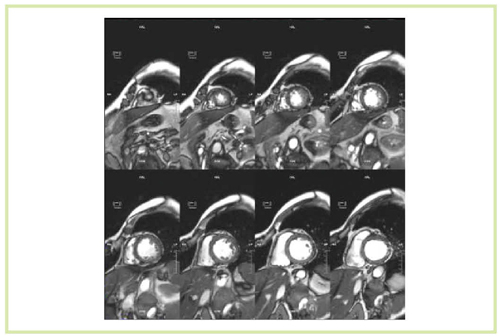

さらに,心臓MRIにおける3T装置の特徴として最も強調すべきは,SNRの高さをthin sliceに生かすことができることである。1.5T装置では,thin slice画像は実用的ではなかったが,3T MRIでは積極的に使えるようになった(図13,14)。thin slice 撮像のメリットを,われわれは心臓の遅延造影法として,whole heart late gadorinium enhancement法に用いることとした。マルチスライスCTの撮影のように,心臓を薄いスライス厚で撮像し,それを再構成することで,短軸像,長軸像,四腔断像など,いろいろな方向からの観察が可能になる。1.5T装置の場合,スライス厚が3mm,スライス間補間が1.5mmであったが,3T MRIではそれぞれ1.5mm,0.75mmとなり,高い空間分解能を持った再構成画像を得ることができる(図15)。

図15 Whole heart late gadorinium enhancement法 a:1.5T,b:3T

図15 Whole heart late gadorinium enhancement法

a:1.5T,b:3T